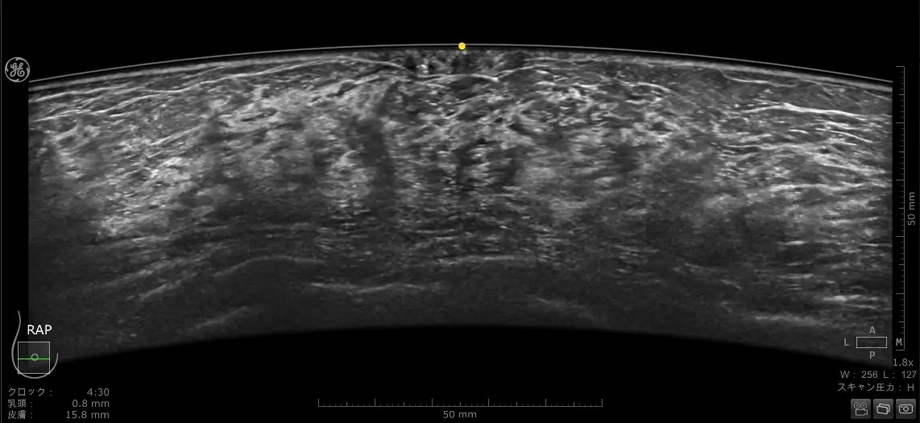

乳房全体を三次元的に自動でスキャンする「Invenia ABUS」は2014年に日本で販売開始以来、改良を重ねてきた。この度販売される「Invenia ABUS Premium」は、ABUSシリーズを8年ぶりに刷新し、初めてAI技術を取り入れた機能*を搭載した最新型モデルである。また、ハードウェアやプローブも刷新され、検査効率・再現性・ワークフローの更なる向上を目指す。

乳房にあてるプローブは、よりフィットするように設計され、周波数帯域も広がったことで空間分解能とコントラスト分解能が向上している。全ピクセルにフォーカスがあたる信号処理、乳頭直下が見えやすくなる画像処理は刷新され、より均一性の高い画像を提供する。